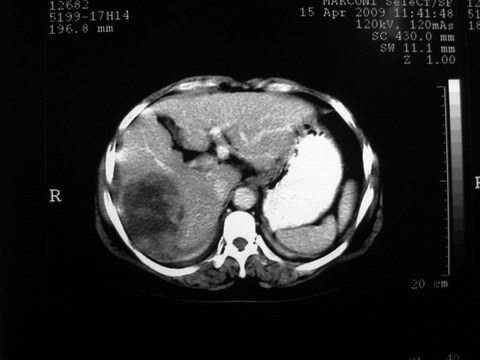

标题: CT19402:肝脏巨大囊实性占位 [打印本页]

标题: CT19402:肝脏巨大囊实性占位

患者 女 51岁 两天前感觉上腹疼,无明显诱因,b超示肝右叶囊实性占位,边缘清楚,其内回声不均匀,ct增强如图,大家看看是什么 ,病人一年前及两月前b超检查只是提示胆囊炎

外院术后,证实肝癌合并出血

本例有2个特点:1,病灶发展迅速,(2月前正常)

2,囊实性,且并边界清晰光滑,呈右后叶赘生性。

可以排除源发肝脏恶性肿瘤和良性肿瘤。

只有转移,出血或炎症可以发展迅速!

特点:1,病灶发展迅速,(2月前正常)[br] 2,囊实性,且并边界清晰光滑,呈右后叶赘生性。囊性区无强化,实性部分较多轻度强化,边界欠清。考虑囊腺癌或囊腺瘤。

出病理 中分化肝细胞癌合并出血